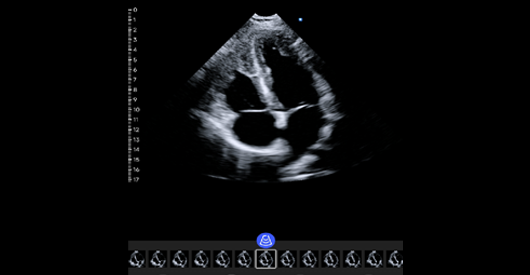

心脏四腔心

阵元基数:64。信号通道:64。